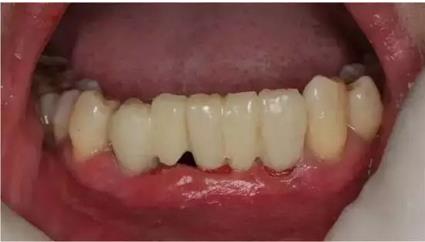

導(dǎo)板就位后逐級(jí)擴(kuò)孔

臨時(shí)冠就位,即刻修復(fù),無(wú)咬合接觸

1:本病例的難度在于高骨密度

的條件下如何順利植入植體

2:數(shù)字化修復(fù)時(shí),

種植臨時(shí)修復(fù)體可能難以就位,

特別是多顆牙的修復(fù)